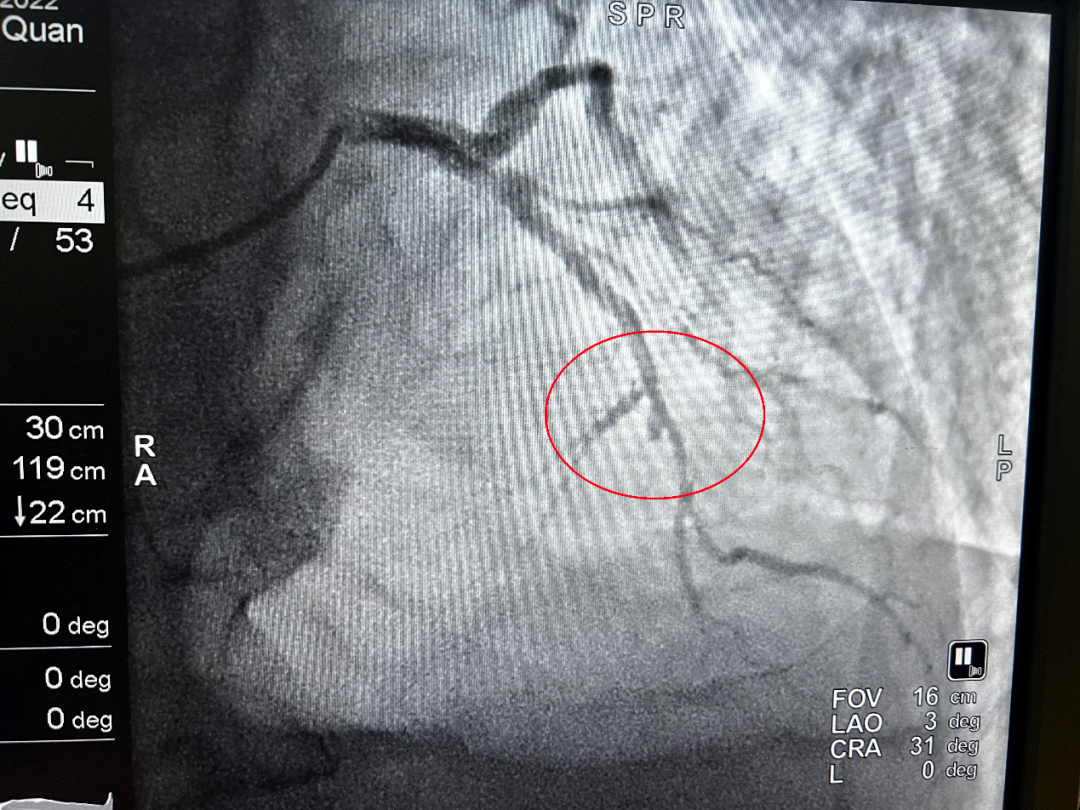

(介入前)

凌晨1點34分,導管室激活;1點38分,患者平車送入導管室;1點48分,穿刺成功;2點01分,導絲通過血管閉塞處……從王大爺首次醫療接觸到導絲通過,僅用時54分鐘。所有醫護人員繃緊神經,爭分奪秒,為患者開辟了一條脫離危險的綠色通道。術后,患者胸痛癥狀明顯緩解,轉危為安。